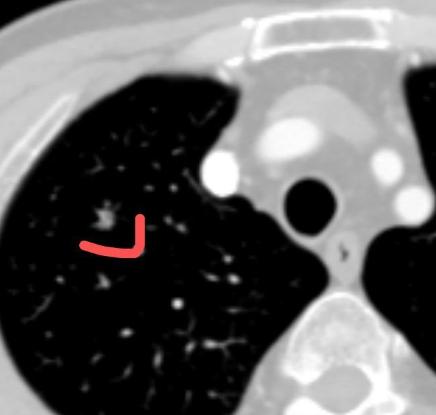

短短6个月,肺结节就从6毫米长到了8毫米?这位患者今年63岁,专程从外地坐飞机来门诊找我。他在体检时查出右上肺有一个实性结节,半年时间就增大了2毫米。 从影像上看,这个结节带有浅分叶,密度也比较高,不少影像科医生都怀疑是早期肺癌,认为发现得很及时。 患者和家属都非常焦虑,态度也很坚决:一定要做手术,他们觉得能这么早发现是“老天帮忙”,必须尽快处理才能安心,再加上看到网上说实性结节很容易出现转移,就更担心了。 虽然结节不大,但位置很深,加上短期内已经出现变化,如果真是肺癌,浸润性和恶性程度可能都不低。如果直接手术,很可能得切掉整个肺叶。 但我心里有些犹豫。因为仔细看影像,结节的边缘其实是光滑的,不能完全排除良性肿瘤的可能。患者已经60多岁,如果直接做肺叶切除,创伤大、恢复慢,对今后的生活质量影响不小。 我认真思索后,建议患者做了三维重建,发现这个结节其实位于右上肺的一个亚段——只需要切除B亚段,范围大约占右肺的5%,比常规的楔形切除范围还小。 这样既能取到组织做病理,也能最大程度保留肺功能。 我们和患者沟通后,决定先做这个亚段切除,术中冰冻病理结果很快出来了:是一个良性软骨瘤。真是非常幸运! 最终,患者只做了一个非常小的切除手术,既明确了诊断,又避免了不必要的肺叶切除。对一位60多岁的老人来说,手术创伤小,恢复也快,基本不影响以后的生活。 这件事也让我再次体会到:作为医生,一定要多站在患者的角度思考,用尽可能小的代价,为他们争取最大的健康获益——这个原则,必须时刻放在心上。[玫瑰][作揖]胸外科乔贵宾医生肺结节[超话]